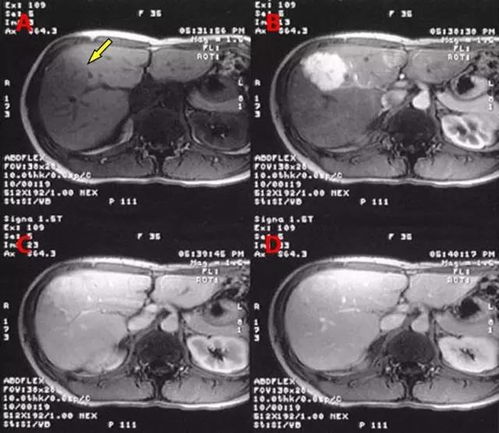

在七台河市人民医院肿瘤外科/肿瘤科,有一支备受赞誉的专家队伍。常春雨主任医师,作为肿瘤科主任和业务副院长,擅长全身恶性肿瘤的手术治疗,尤其在甲状腺、乳腺疾病和肝癌介入手术方面有着深厚的造诣。他多次获得省科技进步奖,丰富的临床经验得到了患者的高度评价,被誉为“妙手仁心”。胡继岭主任医师,作为肿瘤外科副主任,他精通甲状腺、乳腺等良恶性肿瘤的规范化手术及腹腔镜微创治疗。段克旺副主任医师则在甲状腺乳腺肿瘤消融、肝癌介入等领域有着独到的技术。张霞主任医师则擅长恶性肿瘤的综合治疗,特别是在个体化诊疗方案的设计上独领风骚。